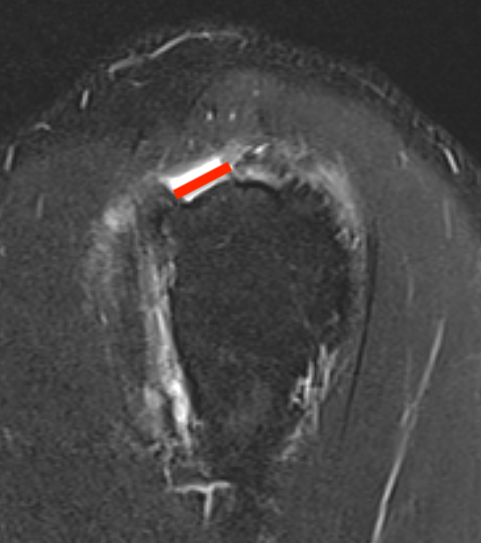

Full thickness rotator cuff tears

Partial bursal sided tear Partial articular sided tears

Small full thickness rotator cuff tear of supraspinatus - retracted to footprint

Large full thickness tear of supraspinatus and infraspinatus tendon - retracted to midhumeral head

Massive rotator cuff tear of the supraspinatus and infraspinatus tendon - retracted to glenoid